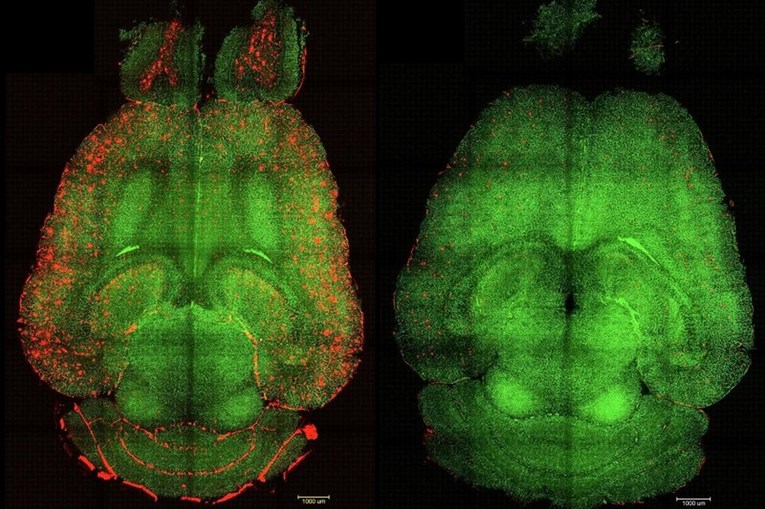

U nizu eksperimenata na genetski modificiranim miševima, koji proizvode velike količine amiloid-beta proteina i pokazuju pad kognitivnih funkcija, primjena supramolekularnih lijekova dovela je do gotovo trenutačnog smanjenja razine tog proteina. “Samo jedan sat nakon injekcije, primijetili smo smanjenje količine amiloid-beta proteina u mozgu za 50-60 posto”, izjavio je koautor i istraživač iz Bolnice Zapadne Kine Sveučilišta Sichuan.

Posebno je uzbudljivo otkriće da su kognitivna poboljšanja kod miševa bila značajna. Miš, čija bi dob bila ekvivalent 90-godišnjeg čovjeka, “povratio je ponašanje zdravog miša” šest mjeseci nakon primanja tretmana. “Dugoročni učinak proizlazi iz obnove vaskulature mozga”, objasnio je Battaglia. “Mislimo da djeluje poput kaskade: kada se nakupljaju toksične vrste poput amiloid-beta, bolest napreduje. Ali kada vaskulatura ponovno počne funkcionirati, počinje uklanjati Aβ i druge štetne molekule, omogućujući cijelom sustavu da povrati svoju ravnotežu.”